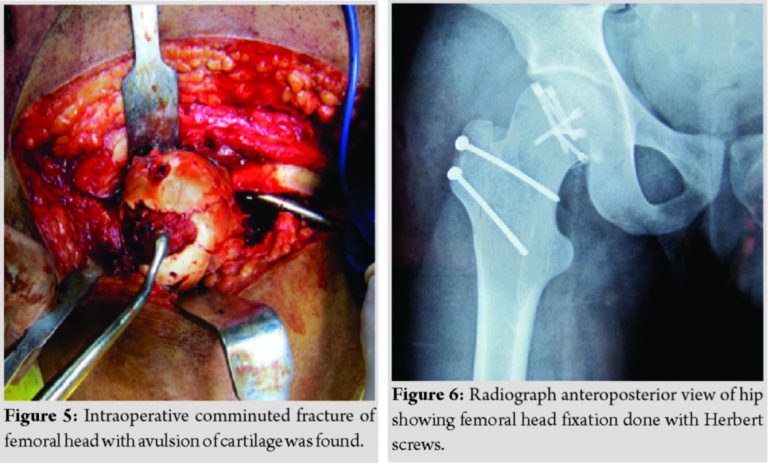

Radiographs done after primary resuscitation as per the standard protocol of advanced trauma life support. Radiographs revealed a fracture at the femoral head (Fig. 1), comminuted fracture Shaft of the mid femur, fracture of lower pole patella, posterior cruciate ligament avulsion with subluxation of the knee joint (Fig. 2), fracture talus, and fracture calcaneus (Fig. 3). There was no dislocation of the hip. Emergent ankle debridement was performed with stabilization of knee by upper tibial pin traction. A computed tomography scan of the right hip joint was done, which was suggestive of the femoral head fracture without dislocation or acetabular fracture (Fig. 4).

Femoral head fixation was performed after the fixation of fracture shaft femur by safe surgical dislocation of the hip approach. Intraoperative comminuted fracture of the femoral head(modified Pipkins type A-V) with avulsion of cartilage was found [5] (Fig. 5). The femoral head was approached by the method of safe surgical dislocation of the hip and fixation done with Herbert screws (Fig. 6).